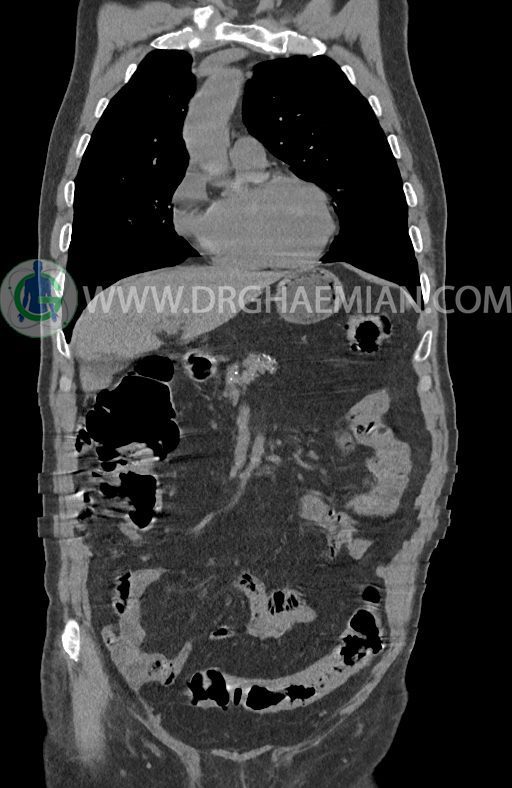

در سی تی اسکن اسپیرال ریه ها و مدیاستن، شکم و لگن با و بدون کنتراست وریدی (مولتی دیدکتور 16 با مقاطع ظریف و بازسازی کرونال) :

–افزایش ضخامت تومورال دیستال مری و GEJ در سگمانی به طول 4cm-5cm (T2 or T3)

-3 لنف نود رژیونال با SAD ≤ 9 mm دیده می شود. (N2)

–آتروفی نسبی پانکراس همراه با فوکوس های کلسیفیه ی منتشر پارانشیم مطرح کننده ی پانکراتیت مزمن

-CBD بسیار دیلاته (16mm) همراه با دیلاتاسیون مجاری داخل کبدی سنترال بدون شواهد سنگ یا توده در مسیر

–کیست های کورتیکال متعدد هر دو کلیه به بزرگترین قطر 56mm

نتیجه : T(2or3)/N2/M0